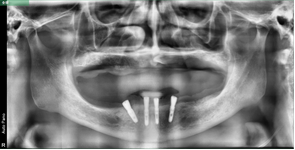

病歷二:

患者,男性,60歲。

主訴:上頜無牙頜,下頜多牙體缺失,余留牙體松動(dòng)不適,進(jìn)食效率低下(困難)明顯,要求治療。

治療方案:完善相關(guān)化驗(yàn)檢查,定制放射導(dǎo)板和種植導(dǎo)板,松動(dòng)牙拔除,并行數(shù)字化全口種植桿卡修復(fù)治療。

術(shù)前片/放射導(dǎo)板定制曲斷片

術(shù)后片/選復(fù)合基臺(tái)(下頜)

桿卡試戴(下頜)/活動(dòng)義齒(上頜)

咬合確定/治療結(jié)束